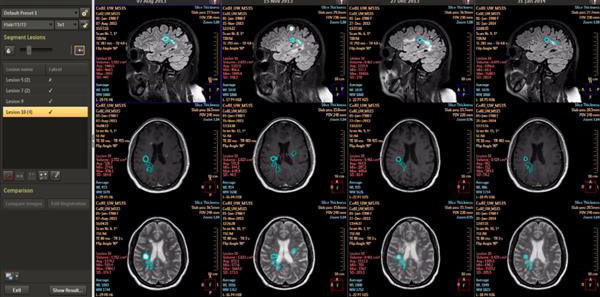

通过新的机器学习能力,IntelliSpace Portal 9.0用纵向脑成像(尚未批准在美国使用)等功能帮助放射科医生检测、诊断疾病并跟进疾病的治疗。纵向脑成像被用来对神经障碍进行纵向评估,这种持续监测功能使得临床医生可以跟踪疾病的发展状况。IntelliSpace Portal 9.0上还有CorTech Labs的测量应用程序NeuroQuant,临床医生可用它来确定脑体积的损失量。